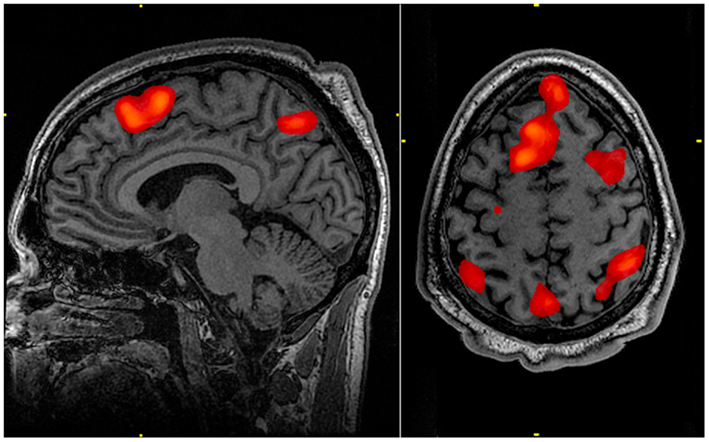

To investigate, my colleagues and I looked at brain images from volunteers scanned using functional magnetic resonance imaging, or fMRI. This technique measures neural activity via blood flow in the brain while people are awake and mentally active. We calculated a “functional connectivity profile” for each person based on their individual patterns of synchronized activity between different parts of the brain.

To analyze the fMRI data for each individual participant, we first divided the whole brain into 268 separate regions. While it’s an open question just how many different functional regions there are in the brain, previous work of ours has shown that using between 200 and 300 regions lets us detect subtle effects, while still keeping things manageable in terms of the time and computing power it takes to run the analyses.

For each pair of regions, we calculated the strength of the functional connection between them. To understand what a “functional connection” is, think of two musicians playing at the same time: rather than measuring how loudly each musician is playing, we measure how synchronized their playing is. It’s not about overall levels of activity in any single brain region, but rather how pairs of regions tend to increase and decrease their activity in tandem. We calculated this measure of synchrony for every pair of regions across a brain. For each person we had a functional connectivity profile for each of the six scans they underwent.

Certain connections were most distinguishing of individuals—namely, those between the brain’s prefrontal lobe (just behind the forehead) and parietal lobe (farther back on top of the head). These areas evolved most recently, and neuroscientists have long known that they are crucial for sophisticated functions like attention, memory, and language.